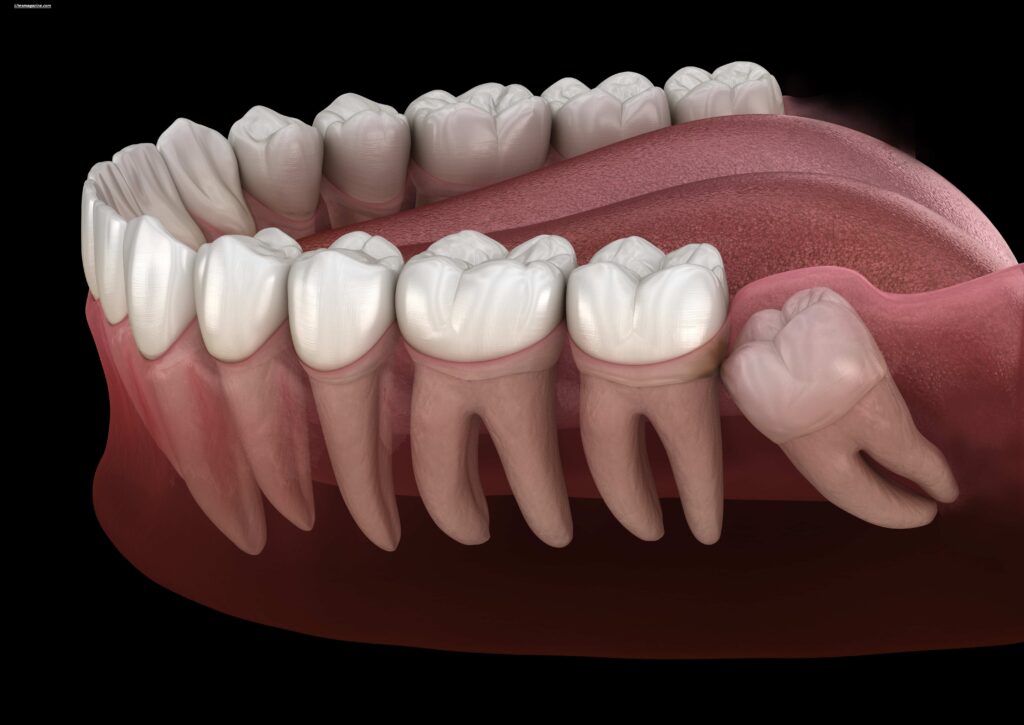

Wisdom teeth are the last set of molars that grow at the back of your mouth. Dentists call them third molars, and they are part of your natural adult teeth. Most people have four wisdom teeth—two on the top and two on the bottom—but some people may have fewer or none at all.

Another important point is that wisdom teeth don’t always grow properly. Because they come in last, there often isn’t enough space in the mouth. This can lead to crowding or other dental issues.

Some people may notice their wisdom teeth coming in earlier, while others may not develop them at all. In some cases, the teeth remain hidden beneath the gums, which is known as impaction.

Today, many people don’t have enough space in their jaws for these late eruption teeth, leading to issues like impaction and misalignment.

Wisdom teeth can lead to several dental issues, especially when there isn’t enough space in the mouth. One of the most common problems is impaction, where the tooth gets stuck under the gums or grows at an angle.

Because these are late eruption teeth, they often struggle to find room to grow properly. This can cause pain, swelling, and even infection.